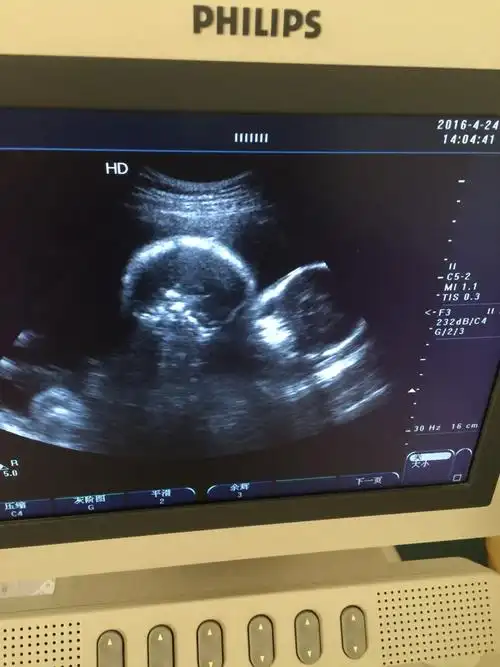

了阳康了旅游和爬山也与我无缘了还有四个月时间再坚持一下#双胞胎

双胞胎超声波

双胞胎宝宝今天的b超终于知道真相了